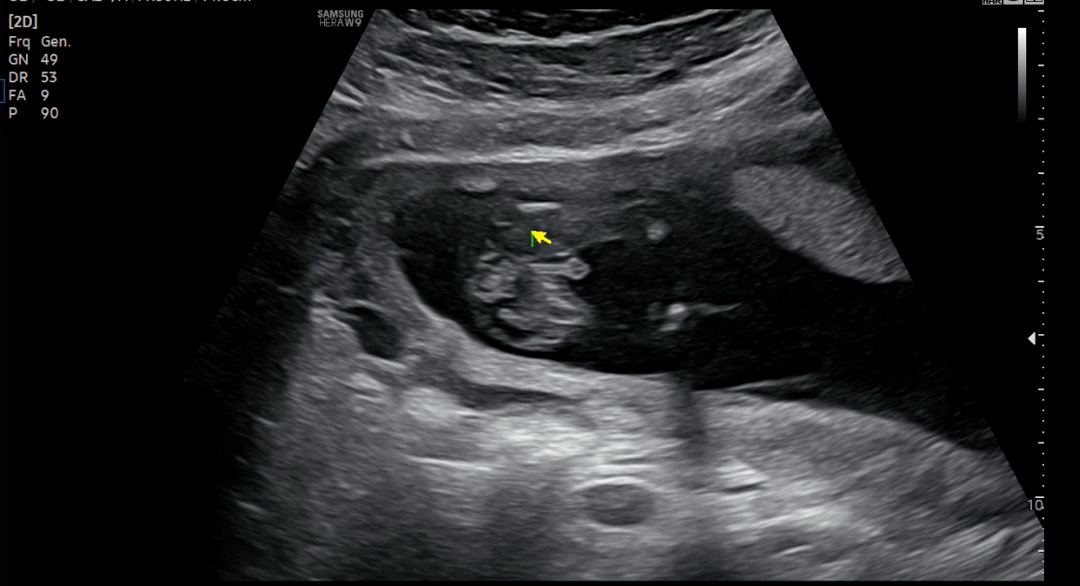

확실한 아들인가요?

이정도면 반전 없겠죠??????